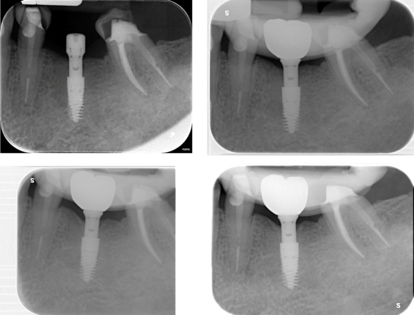

La monoedentulia in sede 35 della paziente viene trattata con impianto GTB T-Zero 3.6 x 9 mm Advan®. L’impianto è posizionato 2 mm subcrestale rispetto alla cresta ossea più apicale (margine vestibolare) e su di esso avvitato GFA Advan® di 5,5mm direttamente in fase chirurgica. A 3 mesi dalla chirurgia viene posizionata corona protesica avvitata in zirconia 550 integrale Katana ® e il follow-up clinico e radiografico è a 6 e 12 mesi dal carico protesico.

A 6 e 12 mesi dal carico protesico si osserva solo un minimo rimodellamento osseo attorno al GFA senza perdita d’osso inter prossimale assenza di sondaggio patologico e di recessione e assenza di alterazioni protesiche strutturali ed estetiche. Questo case report mostra come il GFA ® possa essere una valida scelta nel trattamento delle deiscenze ossee, qualora non si possa usufruire della chirurgia ossea rigenerativa (GBR). Permette di rispettare standard estetici, biologici e funzionali.